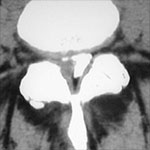

- CT scan and CT angiography

A CT scan is a noninvasive diagnostic test that uses x-rays and a computer to create images of the body. It allows your doctor to view your spine or brain in slices, as if it were sliced layer-by-layer and a picture taken of each slice. This test can help diagnose tumors, hemorrhages, head injuries, and bone abnormalities.